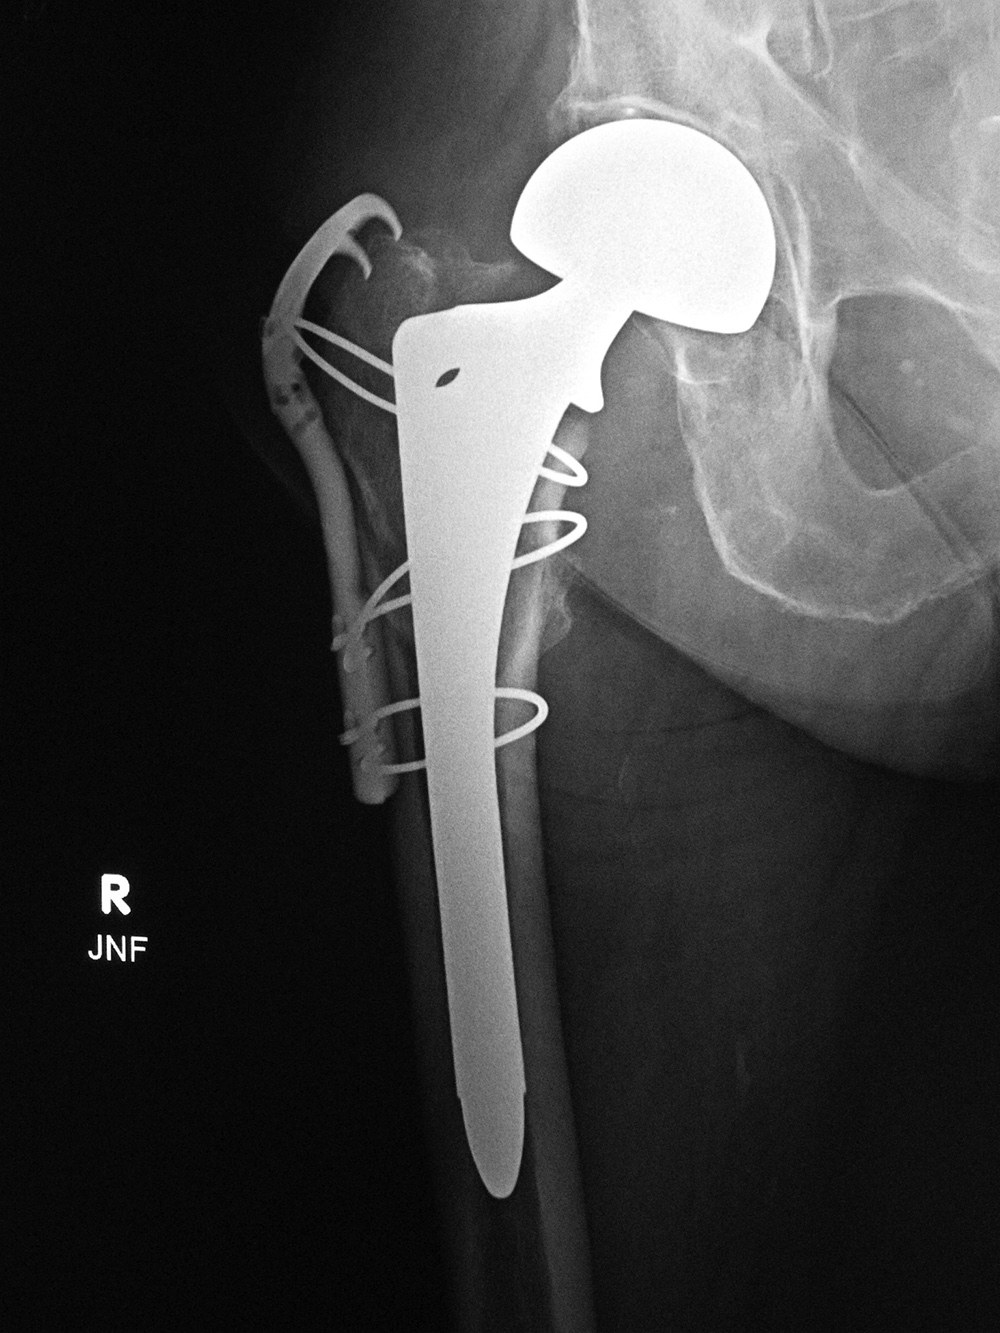

Revision total hip prosthesis |

Triflange acetabular component total hip revision arthroplasty with long femoral stem |

The revision prosthesis was placed because of an earlier periprosthetic fracture. There are two cable wires proximally and two cerclage wires distally. |